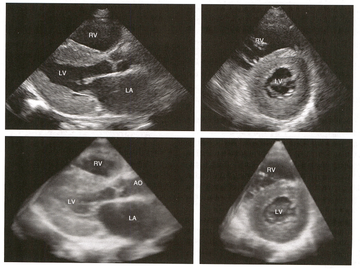

限制型心肌病(Restrictive cardiomyopathy,RCM)是以心室壁僵硬度增加、舒张功能降低、充盈受限而产生临床右心衰症状为特征的一类心肌病。病人心房明显扩张,但早期左心室不扩张,收缩功能多正常,室壁不增厚或仅轻度增厚。随着病情进展左心室收缩功能受损加重,心腔可以扩张[3]